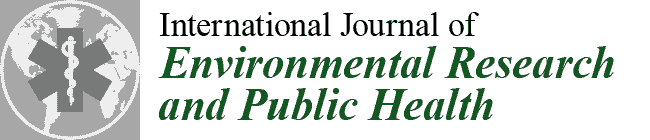

3.3. Fascial Structures and Neural Elements

- Ricci, V.; Özçakar, L. Ultrasound imaging of the upper trapezius muscle for safer myofascial trigger point injections: A case report. Phys. Sportsmed. 2019, 47, 247–248. [Google Scholar] [CrossRef] [PubMed]

- Ricci, V.; Güvener, O.; Özçakar, L. Injections for myofascial pain: From whodunit to an ultrasound-guided technique. J. Ultrasound Med. 2022. [Google Scholar] [CrossRef] [PubMed]